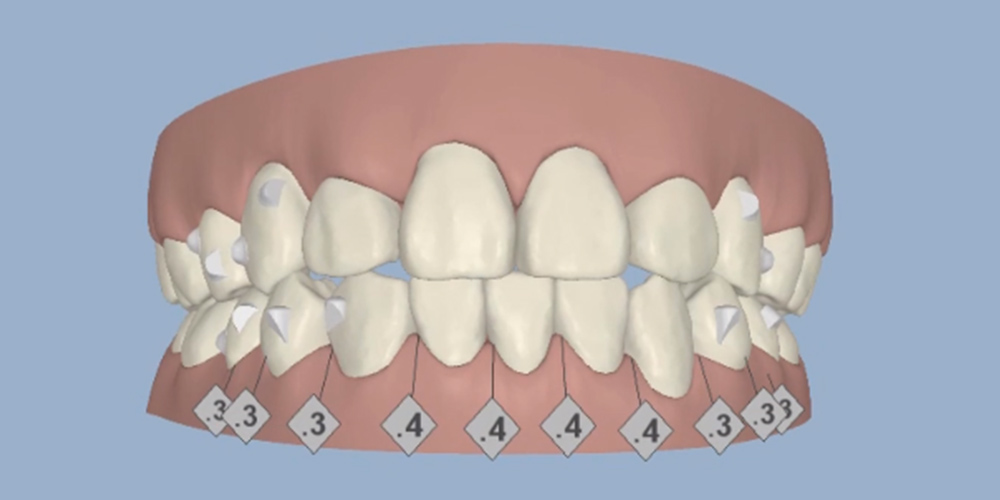

叢生(乱ぐい歯)

歯並びがデコボコに並んでいる状態

| 施術名 | マウスピース型矯正治療 |

|---|---|

| 治療期間 | 1年間 |

| 費用目安 | 440,000円~880,000円 |

| リスク・副作用 | 歯が動くことに伴う痛みや装置の違和感が出る場合がある |

| お支払い方法 | 各種クレジットカード・ローン支払い対応 |

| 症例数 | 累計5,000件以上(2009年~2021年12月までの累計) |